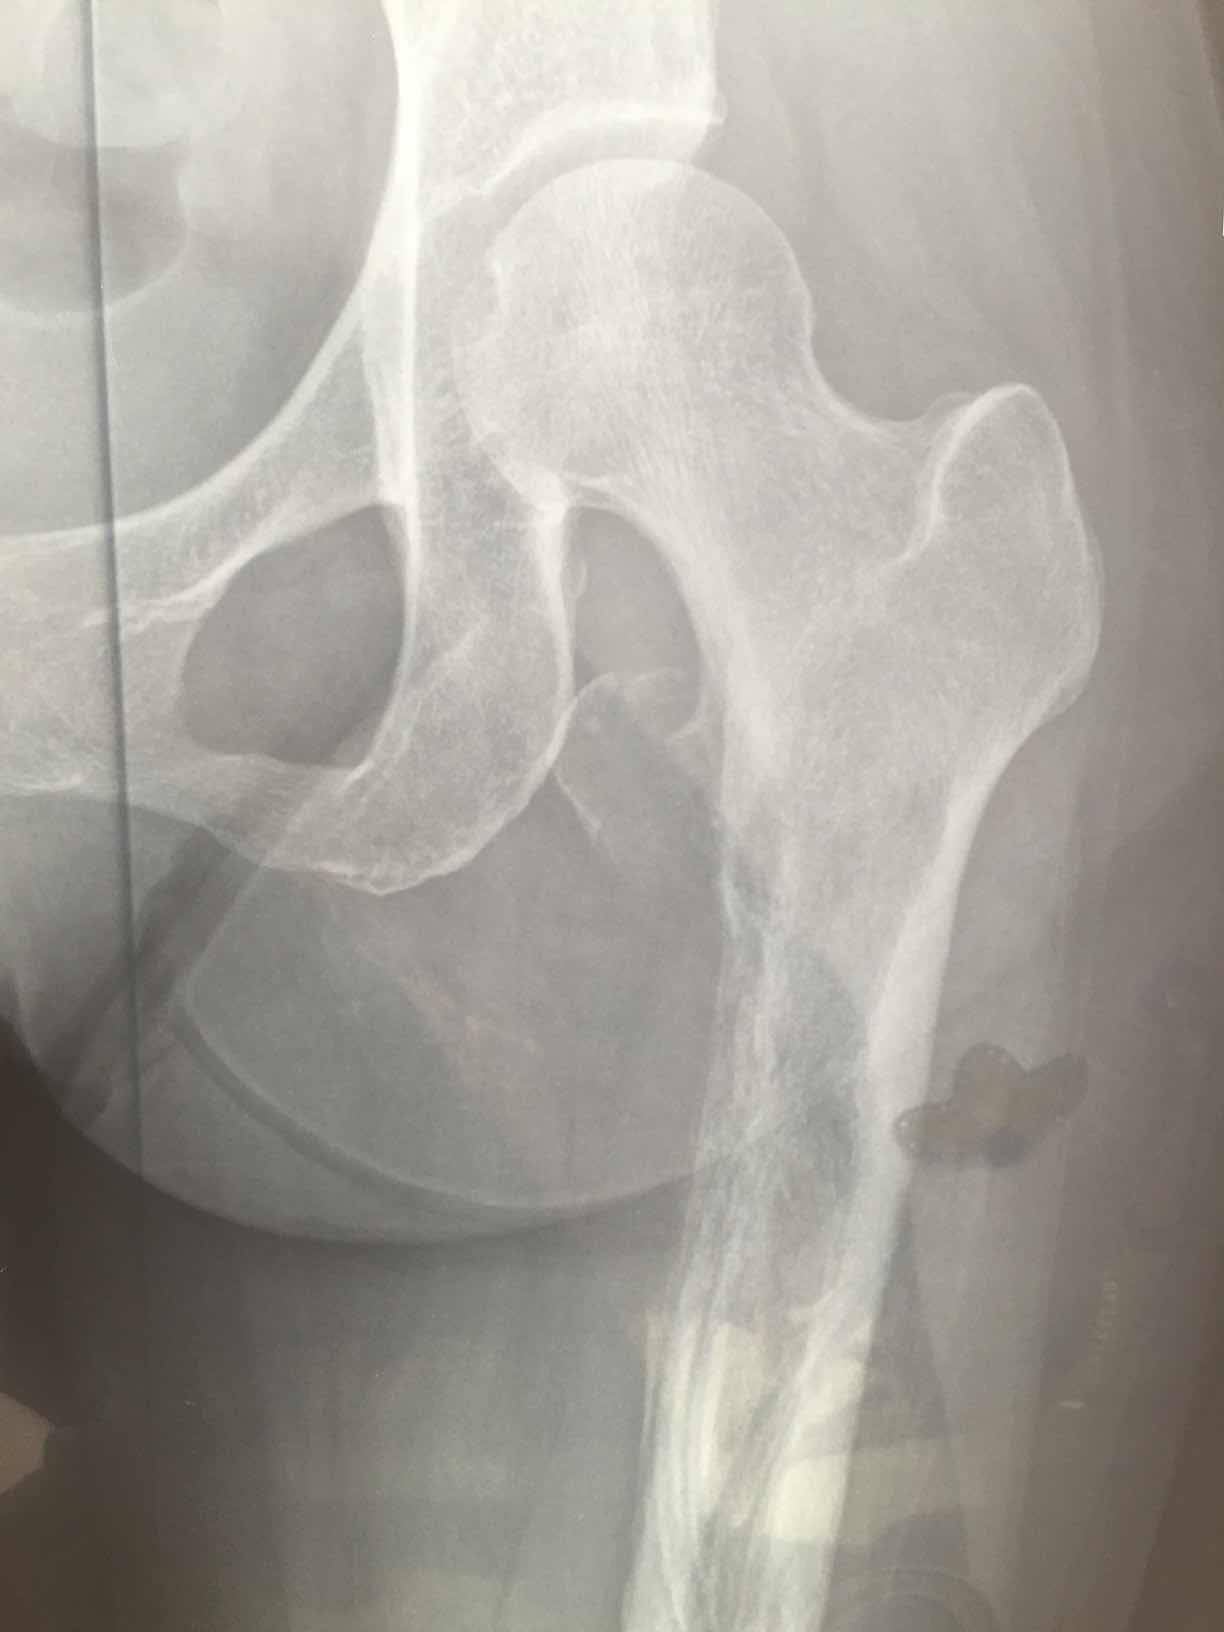

这是第一次确诊是拍的腿部ct,因为是腿疼才去检查,直接去的骨科医院,没想到确是转移,主要是左大腿疼痛,在家以为是腰间盘卧床躺了3月,期间就第三个月疼痛无比,刚开始两月还好,也能行走,就是腿疼,尽量不走,等再去医院检查的当天还把左大腿根掰了下,可能造成了骨裂,图片为最后一张图画圈的那里,打了两次骨转针。吃了一个月易瑞沙,腿已经不疼了,但是由于骨裂那块,还是卧床不让行走,医生也说让静养,怕骨折。我想问问大家有没有这方面的,我家这个情况该怎么办。还有机会在站起来行走吗,目前左腿肌肉萎缩的还比较厉害,拜托大家。

是股骨头处骨裂?